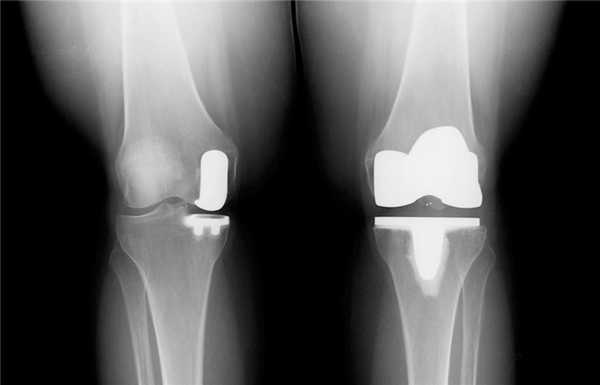

Результат частичной замены коленного сустава на рентгене.

Частичный и тотальный способ.